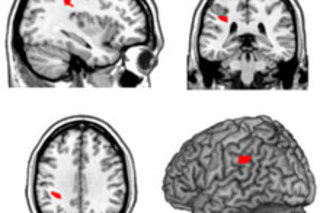

人类大脑是否有一个“上帝之眼”——一个负责调节灵性感受和宇宙连接感的特定区域?一年前,《DISCOVER》曾报道过一项关于有灵性人群的科学研究,该研究 未能确定大脑中的一个特定区域 是控制宗教情感的关键。但现在,一项新的 研究 提出,大脑的物理构成与人们对宗教和灵性的态度之间存在联系。通过观察脑癌患者手术前后的大脑,意大利的研究人员发现,大脑后部区域,特别是称为顶叶皮层的区域,受损后会增加患者“自我超然”的感受,即与宇宙合一的感觉。顶叶皮层是通常

参与维持自我意识的区域,例如通过帮助你追踪身体部位。它也与祈祷和冥想有关[New Scientist]。

这项由意大利乌迪内大学心理学家 Cosimo Urgesi 领导的研究,对88名脑癌患者在手术切除肿瘤前后进行了调查。他们填写了一份关于他们信仰的问卷,其中包含一个部分用于衡量他们的“自我超然”程度。“自我超然”得分高的人,会在回答诸如“我常常感到与周围的人如此亲近,感觉没有分离感”;“我感到与大自然如此契合,以至于万物都像一个单一的有机体”;“我沉浸在当下,与时间脱节”这类问题时回答“是”。同样的人也倾向于相信奇迹、超感官知觉和其他非物质现象

科学家发现,在手术前,患有顶叶皮层肿瘤的患者报告的自我超然水平高于患有额叶皮层肿瘤的患者。肿瘤切除后,顶叶皮层患者的自我超然得分更高,而额叶皮层患者则没有变化。

研究人员表示,这些发表在《神经元》杂志上的 研究结果 表明,

顶叶皮层选择性损伤导致宗教性和灵性明显增强。接受顶叶皮层肿瘤切除的患者在面对关于他们的死亡和健康的不利消息时,处理得更好;而额叶皮层出现问题的患者则对健康问题更加愤世嫉俗。Urgesi 推测,

图片:Cosimo Urgesi